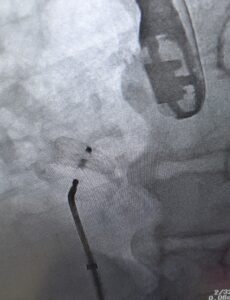

PFO閉鎖デバイス

(今回はアボット社のデバイス)